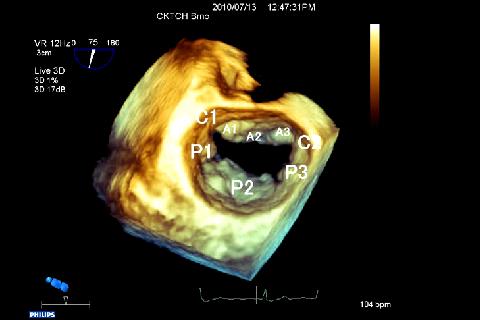

CARDIO3® Atlas of Three-dimensional Echocardiography - reference/learning tool for cardiologists, cardiac surgeons, internists, other physicians, and sonographers evaluating 3D echocardiograms for ultrasound diagnosis.

In our atlas we have collected typical as well as rare and sometimes even bizarre of real-time three-dimensional transesophageal echocardiography (RT-3D TEE) findings we meet in daily routine.

The first chapter deals with mitral valve pathology and is subdivided into several sections: normal mitral valve and functional regurgitation, prolapse, Barlow disease, infective endocarditis, mitral stenosis, mitral valvuloplasty ring, mitral prosthesis (mechanical and biological) and various.